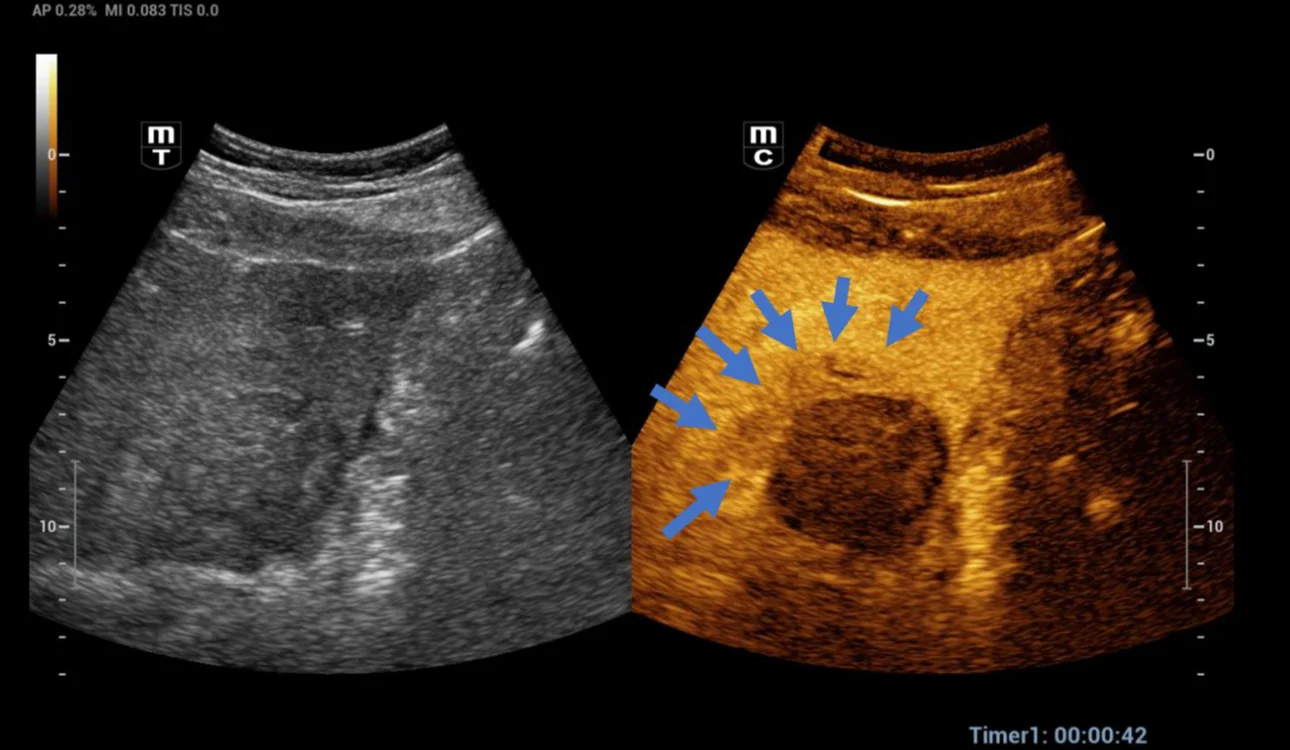

After a month, a CEUS exam was performed to assess the post-thermal ablation zone. The post-thermal ablation zone in the arterial phase after injection of 1.2 ml of Sonovue intravenously (Fig 2). A clear margin of necrosis developed from post-thermal ablation was visible. The necrotic region didn’t undergo contrast enhancement in any phase of the examination. In the portal phase (Fig 3-4), contrast washout was observed in the liver parenchyma adjacent to the ablation zone (arrows). Then a CT scan was performed to verify the case (Fig 5). A hepatic vein adjacent to the post-thermal ablation recurrence area was visible.

Fig. 3 In the portal phase (42th second), contrast washout was observed in the liver parenchyma adjacent to the ablation zone (arrows).